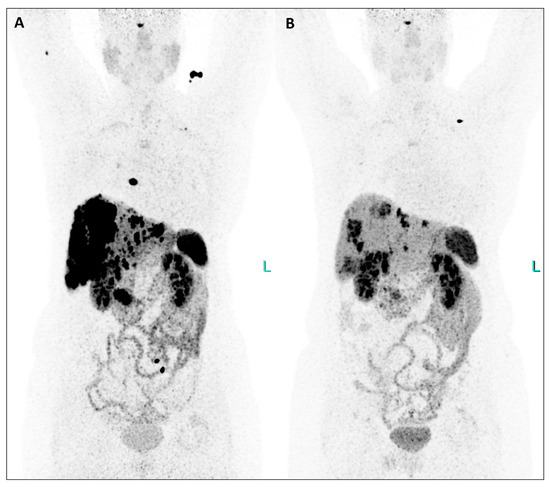

Figure 2. This extraordinary response to TANDEM-PRRT involving pancreatic tumor, liver, lymph nodal, and bone metastases was also demonstrated by comparing [64Cu]Cu-DOTATATE PET/CT from February 2023 ((A), MIP) and January 2024 ((B), MIP), the latter performed two months after the third PRRT (Figure 2).

Figure 3. An extraordinary reduction in the uptake of the radiotherapeutic compound is evident in both the primary tumor and all metastatic lesions when comparing MIP images from post-therapeutic single-photon emission tomography/computed tomography (SPET/CT) (Figure 3, (A), July 2023; (B), September 2023; (C), November 2023). Furthermore, hepatomegaly is no longer present after therapy, and the bone lesions have completely disappeared. Equally significant, since the initiation of therapy, the patient has gained weight, experienced a notable reduction in abdominal pain, and seen improvement in her energy levels, enabling her to resume physical activity and engage in everyday life activities. Additionally, their serum biomarkers exhibited a substantial decrease throughout the TANDEM-PRRT courses: neuron-specific enolase decreased from 418 ng/mL before therapy to 25.8 ng/mL (a reduction of 93.8%), and Chromogranin A decreased from 2950 ng/mL to 270 ng/mL (a reduction of 90.8%).